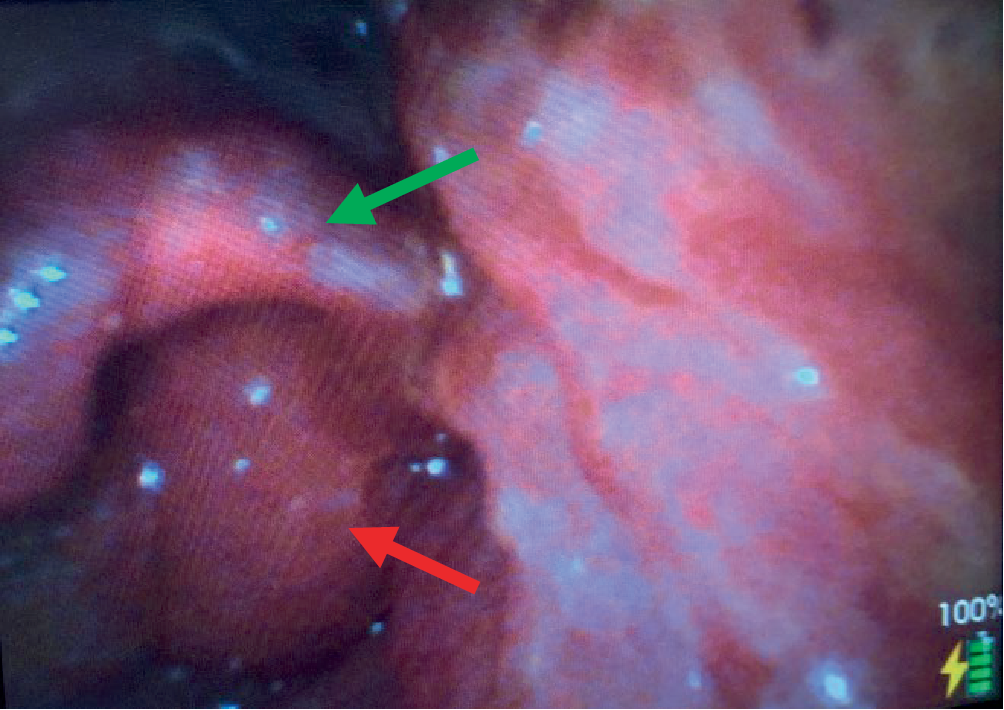

Bei der im kurzfristigen Verlauf progredienten Lippenschwellung und den massiven Schmerzen der Patientin fiel die Entscheidung zur Narkoseeinleitung und Intubation in Koniotomiebereitschaft. Neben enoralen Schleimhautverletzungen zeigte sich in der Videolaryngoskopie eine deutliche Schwellung von Epiglottis und Aryknorpeln (Abb. 1). Die endotracheale Intubation gelang schließlich mit einem kleinlumigen Endotrachealtubus (ET, Innendurchmesser [ID] 6,0 mm). Hierüber war eine suffiziente Beatmung möglich, es bestand klinisch kein Hinweis auf eine Aspiration. Die Kreislaufsituation ließ sich durch Volumengabe und niedrig dosierte Katecholamintherapie stabilisieren. Unmittelbar nach Atemwegssicherung wurde im Schockraum eine Gastroskopie durchgeführt. Diese ergab ausgedehnte Schleimhautablösungen und nekrotische Areale der Schleimhaut von Ösophagus und Magen, welche bis in das Duodenum reichten (Grad 2b bis 3b nach Zargar [1], Abb. 2). Die sich im Bereich des Magenkorpus und -fundus befindliche Flüssigkeit, bei welcher es sich mutmaßlich noch um Reste des in Wasser aufgelösten Abflussreinigergranulats handelte, wurde vollständig abgesaugt. In der anschließend durchgeführten Computertomographie (CT) des Thorax und Abdomens kamen ausgeprägte ödematöse Veränderungen im Bereich von Pharynx und Larynx sowie der Wand von Ösophagus und Magen zur Darstellung. Eine Hohlorganperforation oder eine aktive Blutung konnte ausgeschlossen werden. Bei mäßigen pneumonischen Infiltraten beider Unterlappen bestand der Verdacht einer Aspirationspneumonie, ein Lungenödem bestand nicht.

Abb. 1

Videolaryngoskopische Sicht (Aryknorpel [roter Pfeil] und Epiglottis [grüner Pfeil])